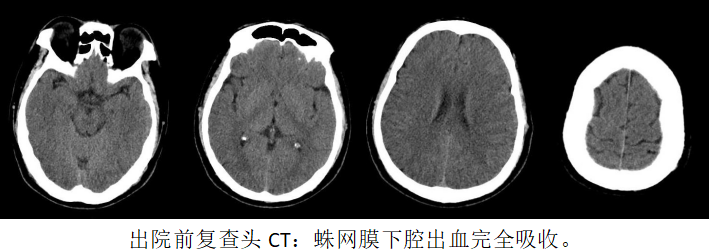

神经重症术后管理是摆在面前的第二座大山,孟先生颅内尚存大量积血,医疗团队即刻在无菌条件下为患者放置腰大池引流及颈内静脉置管,返回监护室后又进行腰大池持续引流、脱水降颅压、改善脑血管痉挛、镇痛等治疗。术后第一天复查,脑CT提示出血减少,术后第二天孟先生意识清醒,评估条件允许后拔出气管插管,术后第三天引流脑脊液颜色变浅,术后第七天拔出腰大池引流管,术后第十六天孟先生完全恢复正常并顺利出院。